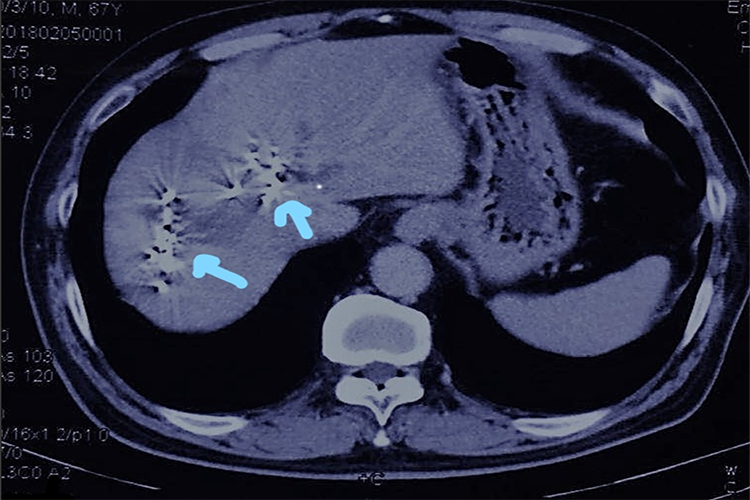

血行转移:肾细胞癌先侵犯肾静脉,导致静脉内形成癌栓,还可向远处转移到肺、肝、骨骼等处。